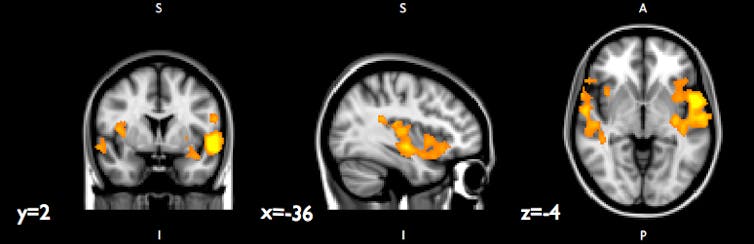

About four years after they took the community violence survey, when the youth were around 17 years old, we asked 22 of them to lie down in a magnetic resonance imaging (MRI) machine while we scanned their brains. When we examined the images we’d collected, we zeroed in on two small but critically important structures near the base of the brain: the hippocampus and the amygdala.

In addition to looking at the size of the hippocampus and amygdala, we also looked at patterns of interconnection between these structures and other regions of the brain. Which parts of the brain “talked” more to each other, as reflected by more tightly correlated levels of activation?

We also found that, among youth exposed to more community violence, the right hippocampus showed stronger connections with other brain regions linked to emotion processing and stress, perhaps suggesting that these youth were more vigilant to potential threat. If you’re used to encountering dangerous situations, maybe you and your brain learn to stay alert to avoid the next potential threat that lurks around the corner.